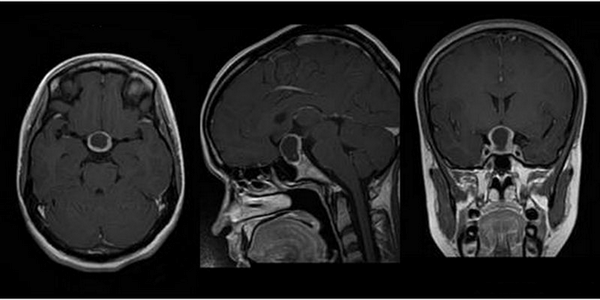

МРТ гипофиза при краниофарингиоме: сканы в разных проекциях

Магнитно-резонансная томография - один из высокоинформативных способов инструментальной диагностики. Исследование показывает мельчайшие изменения в структуре органов, предположительный характер патологии, взаимоотношение с близлежащими структурами. Скульптурирование многоплоскостных изображений во время МР-сканирования подразумевает использование принципа ядерно-магнитного резонанса, но не рентгеновских лучей. Атомы водорода в клетках воды, попав в поле, генерируемое аппаратом, начинают перестраиваться, при обретении привычного положения выделяется определенное количество энергии, которое фиксируют датчики, а обрабатывает компьютерная программа. Какого-либо вредоносного воздействия на организм во время диагностической процедуры нет, при условии отсутствия в теле металлических составляющих. Врач получает возможность рассматривать патологический очаг в любой плоскости, что невозможно при обычной рентгенографии или КТ.